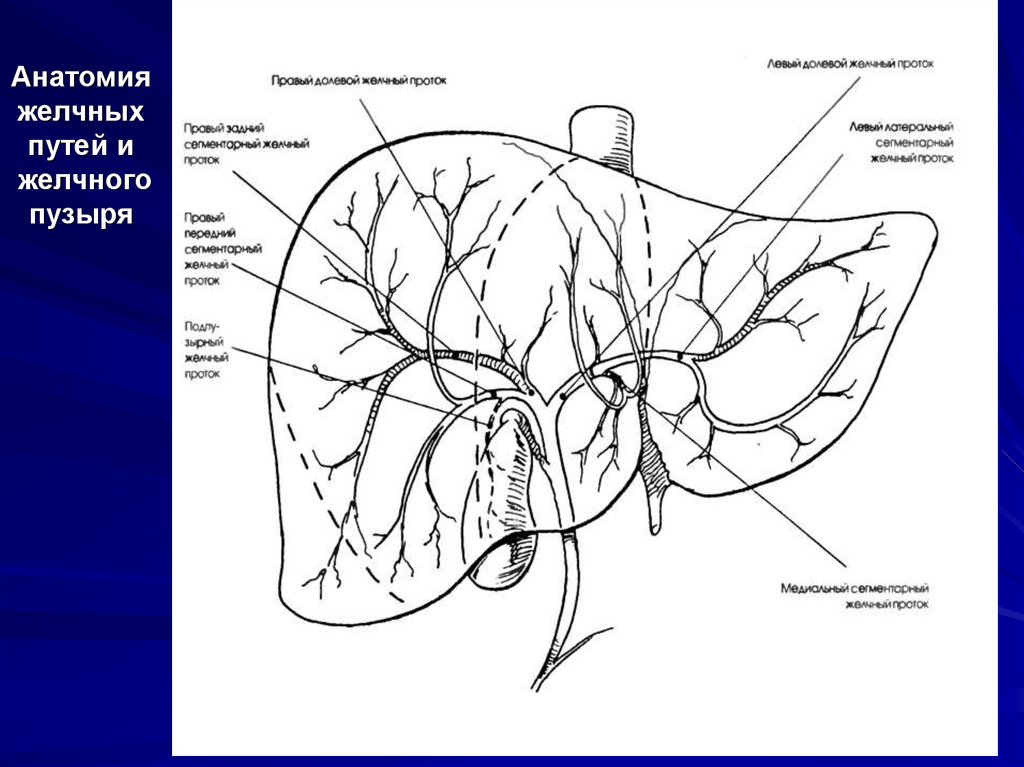

17. Анатомия желчных путей и желчного пузыря

18. Анатомия желчных путей и желчного пузыря

8. Анатомия

Желчный пузырь — это полый орган,

похожий на мешок, имеющий в длину 10

см, который находится в ямке,

располагающейся на анатомической

границе между правой и левой долями

печени. Внепеченочный сегмент

желчного пузыря покрыт брюшиной.

9.

Желчный пузырь имеет дно, тело,

воронку и шейку. Дно закругленный

слепой участок желчного пузыря,

который выступает немного за край

печени. Тело составляет главную часть

желчного пузыря. Шейка представляет

собой узкий сегмент желчного пузыря,

расположенный между его телом и

областью пузырного протока. Воронка,

известная как карман Гартмана,

представляет собой небольшой

луковицеобразный дивертикул.